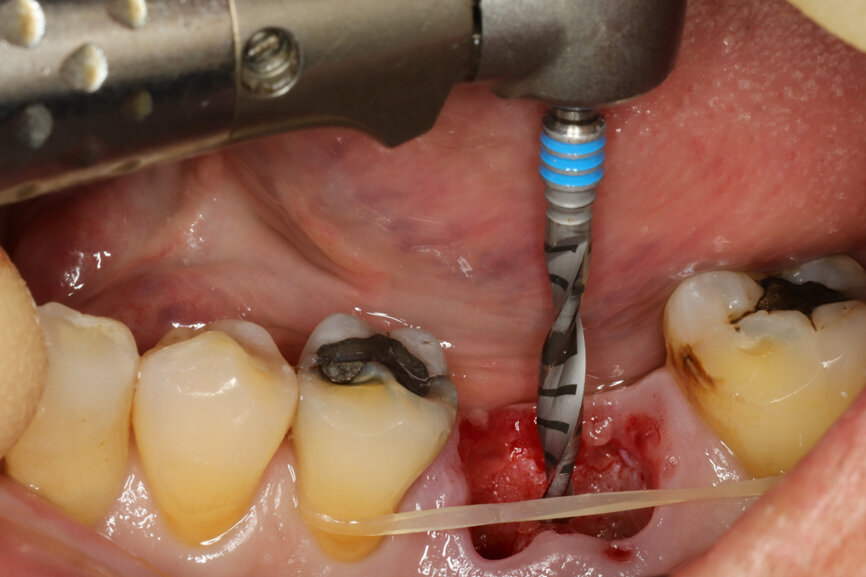

Fig. 4: Root splitting for minimally traumatic extraction.

Fig. 6: Osteotomy with the ⌀ 2.2 mm drill.

Fig. 7: Centrally oriented osteotomy.

Fig. 8: Alignment of the ⌀ 2.2 mm drill, confirming 3D position.

Fig. 9: Alignment of the ⌀ 2.2 mm drill, confirming 3D position.

Fig. 10: Osteotomy with the ⌀ 2.8 mm drill.

It was possible to verify solid interradicular bone availability (Fig. 5), extending further the limits of the root apices and allowing for a centrally oriented osteotomy. The implant bed preparation started with the use of a needle drill at 800 rpm, followed by the ⌀ 2.2 mm and ⌀ 2.8 mm drills (Figs. 6–10). The implant was placed with the use of ratchet and torque control, reaching the desired final position at a 50 N cm torque value (Figs. 11–13). The socket was then augmented with bovine-derived bone substitute impregnated with advanced platelet-rich fibrin (A-PRF) and finalised with sutures to keep the A-PRF application immobile, and a 3 mm healing abutment was placed (Figs. 14–17).